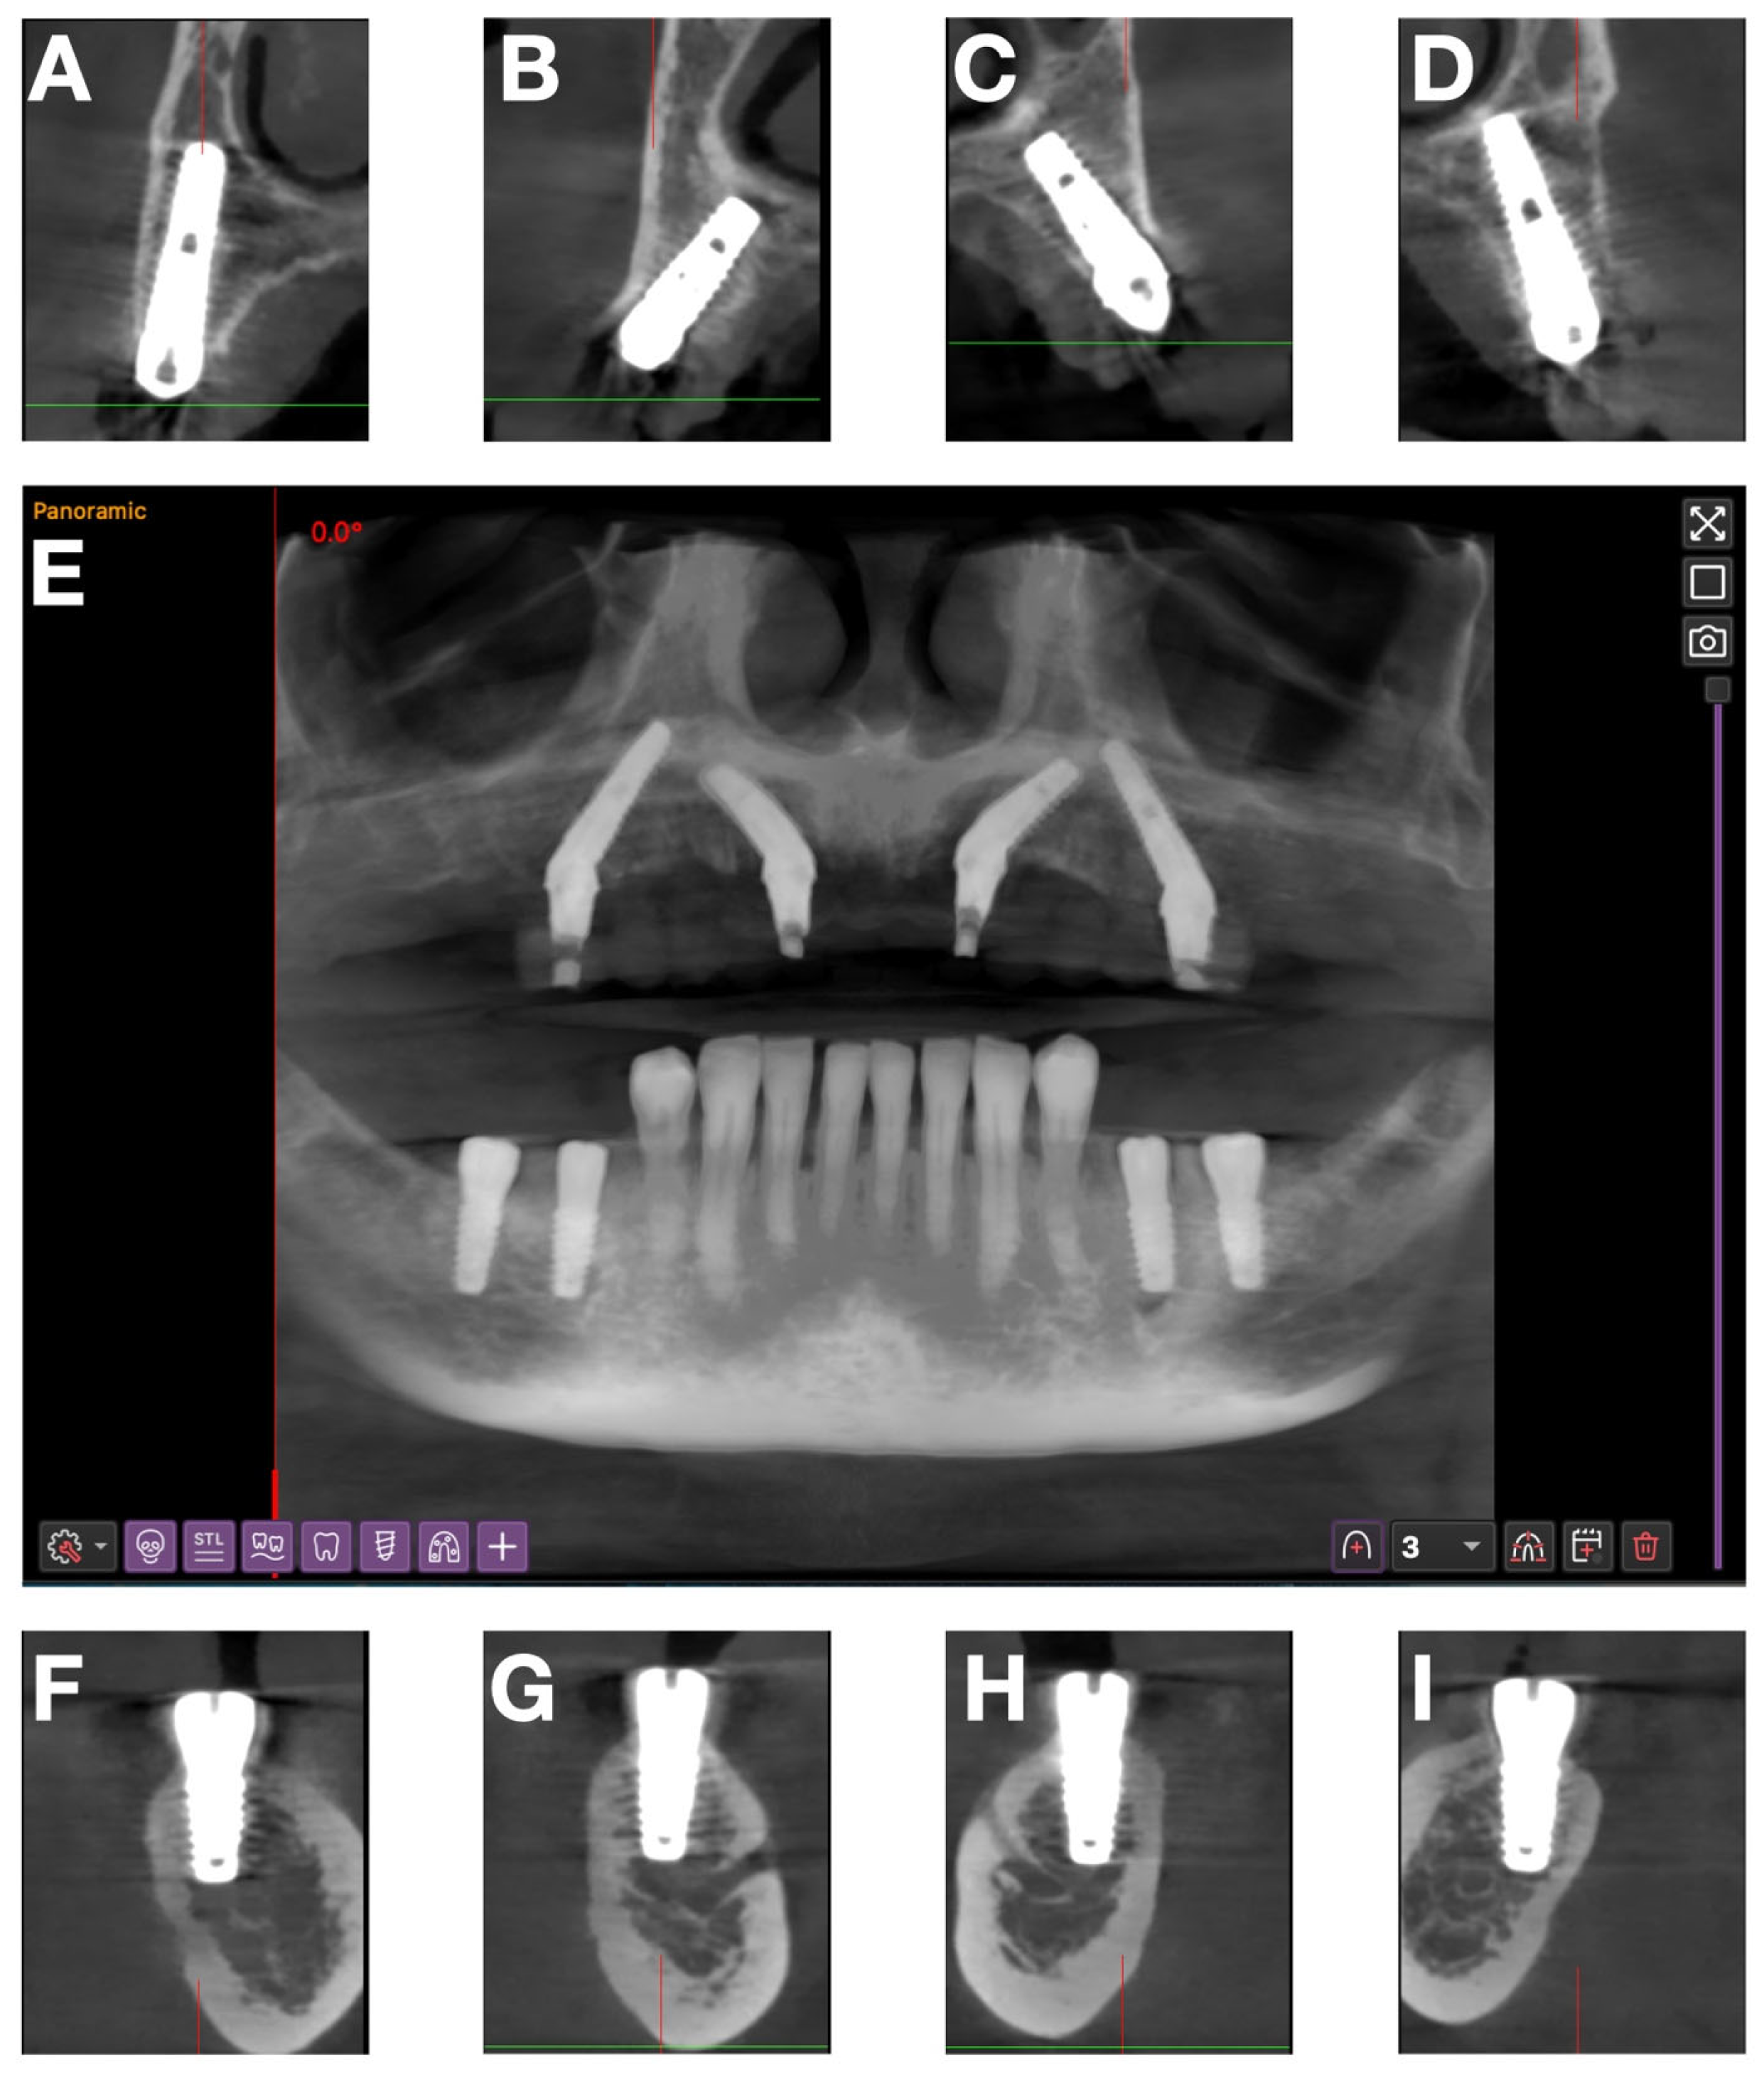

For a precise 3D assessment, a full CBCT scan was performed (Figure 3A). The images were analyzed for alveolar ridge morphology, sinus dimensions, mandibular canal position, and available bone height and width.

A multiplanar analysis performed in Implastation revealed moderate anterior ridge resorption and accentuated posterior atrophy. Therefore, an All-on-4 “M” configuration was chosen, in which anterior implants were tilted mesially and posterior implants distally to avoid the maxillary sinuses (Figure 4).

These qualitative observations were corroborated with the postoperative CBCT evaluation (Figure 11), which showed correct 3D alignment, parallelism of the anterior and posterior implants, and anatomic safety zones.

Figure 11. Postoperative CBCT: (AD) sections at the level of maxillary implants 16, 12, 22, 26; (E) panoramic view; (FI) sections at the level of mandibular implants 46, 45, 35, 36.